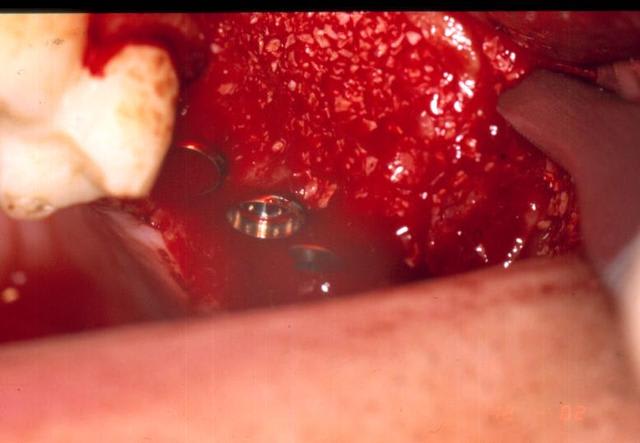

29/04/2005 à 12h42

et encore

Comblement aujlvz - Eugenol

Sutures vzgxss - Eugenol

Radio1 nedqqo - Eugenol

Radio2 jxft6m - Eugenol

merci les gars. dans ce cas, et presque tous mes sinus, c'est du bio-oss à 100%.

ayant posé des branemark pendant des années, je n'aurai effectivement jamais osé faire ça avec une structure purement cylindrique, le grip du micro-thread conique est vraiment sympa et rassurant. quant au rapport diamètre longueur, généralement c'est entre 13 et 15 dans un sinus. là, le diamètre du col est 4.5, et le diamètre du fût est de 3,5. échaudé par mon expérience et celle de quelques copains avec les implants trop larges, et par intuition, mais il doit y avoir de la litérature, je pense que la micro-circulation se rétablit plus facilement et plus rapidement autour de diamètres moins importants.